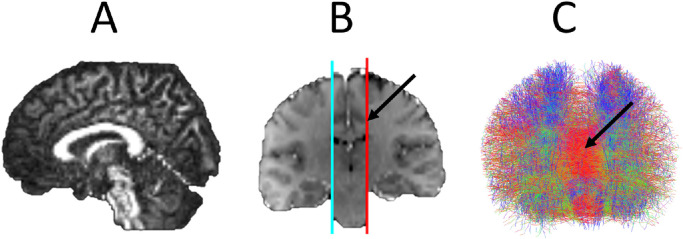

Fig. 3.

Legend: Probabilistic fibre tractography of interhemispheric connectivity. A) FA image in sagittal place revealing corpus callosum. B) Coronal T1 image registered to FA image with the seed (cyan) and inclusion (red) regions drawn manually on a paramedian sagittal plane at the level of the depth of the cingulate sulcus (arrow). These seed plane depicts the voxels from which streamlines are generated and the inclusion place depicts the voxels through which these streamlines must pass to be selected. C) Anterior view of resulting tractography consisting of 5000 streamlines with corpus callosum fibres visible in red (arrow).